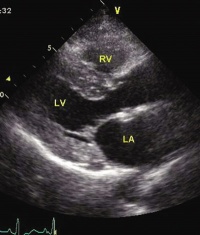

左心室的B超现象图

这亦反映左心室在泵血过程中会造出比右面多五倍的压力。在每一次心跳中,左心室会接受来自肺静脉大约处於80托(相当於接近11千帕斯卡的压力)的血,接著把血压推高至大约120托(相当於16.3千帕斯卡)以将之送入大动脉。(所有压力值是在心脏处於休息状态下量度,亦为与被订为零的参考压力的周边大气层压力相对的相对值。)